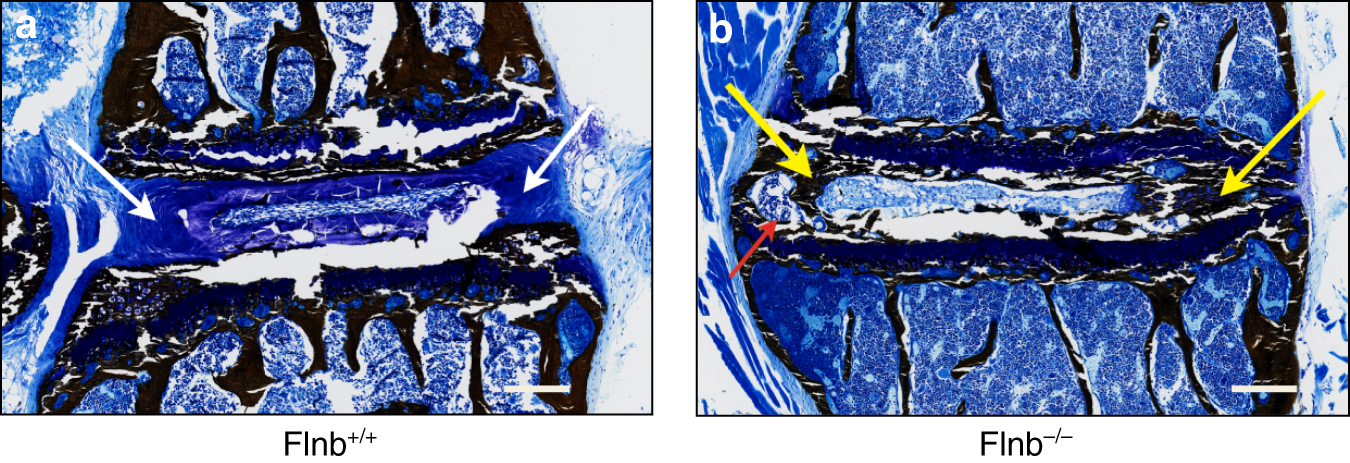

Fig. 1

Flnb−/− IVD exhibits ectopic mineralization. a, b P21 IVD plastic sagittal sections with Von Kossa staining. a Flnb+/+ IVD exhibiting blue–violet fibrocartilage in AF IVD tissue (white arrows). b Flnb−/− IVD exhibits black–brown staining in the AF representing mineralization of the AF tissue (yellow arrows). AF also exhibits the characteristics of trabecular bone, an indication that it is undergoing full ossification. n = 3, Representative image of T7-T8 IVD in individual mice